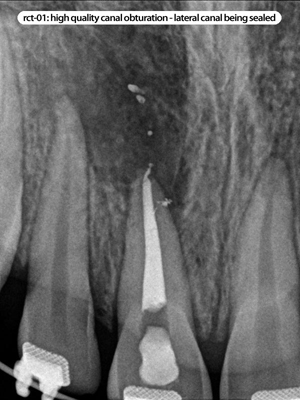

Root Canal Cases